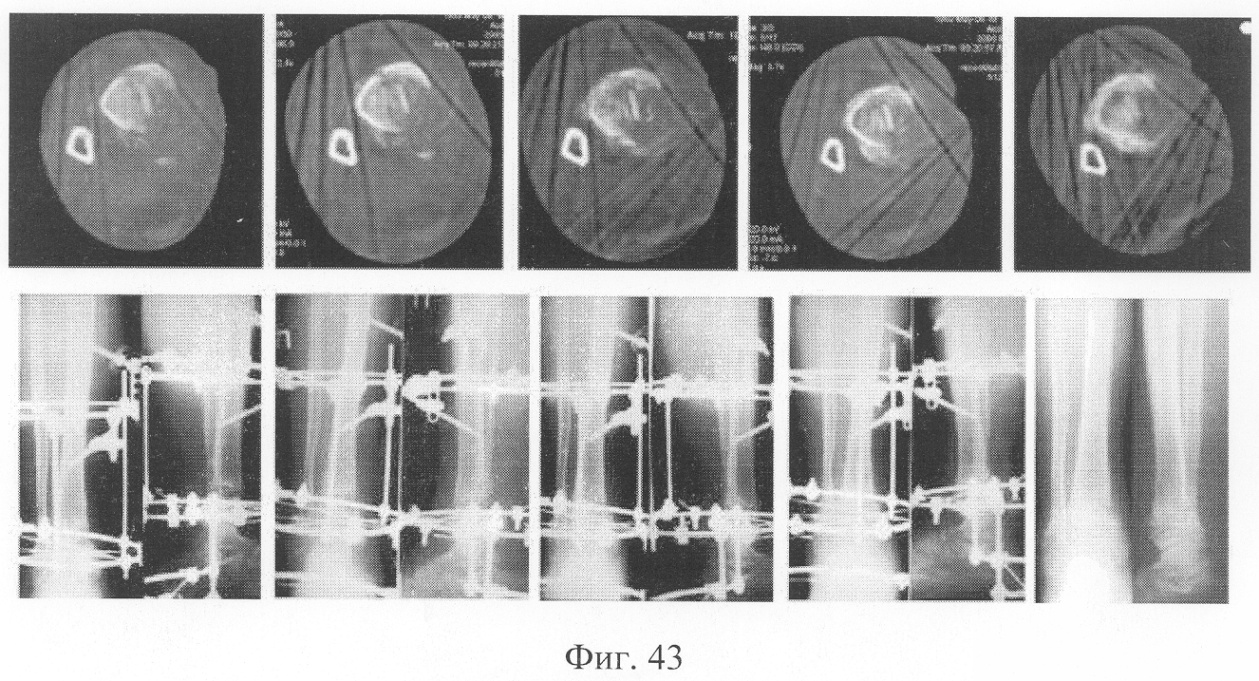

При рентгенологическом и томографическом контроле в динамике отмечалось отчетливое нарастание плотности костной ткани в трансплантатах без предварительной резорбции (фиг.43 – динамика рентгенологической и томографической картины). Таким образом, развившиеся воспалительные процессы были своевременно купированы и не сказались на результате лечения (фиг.44-46 – результат лечения).